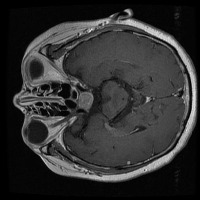

Early Detection of Brain Tumors: Use the "tesis" model to analyze MRI scans of patients proactively during routine check-ups, helping in the early identification of the presence of lesion selar or tumor hipofisario, leading to timely and potentially life-saving interventions.

Assisting in Treatment Planning: Oncologists and neurosurgeons can use the "tesis" model to study the location, size, and class of a patient's tumor. This helps in determining the best treatment options and surgical approaches, ultimately improving patient outcomes.

Medical Education and Training: Incorporate the "tesis" model in medical school curricula and professional trainings aimed at educating future doctors and radiologists about the identification and treatment of lesion selar and tumor hipofisario.

Research Tool for Cancer Studies: The "tesis" model can serve as a tool for researchers working on experimental treatments or clinical trials focused on lesion selar and tumor hipofisario. By identifying tumor classes efficiently and consistently, the model can help researchers compare treatment efficacy and study tumor progression over time.

Second Opinion Provider: Medical professionals can use the "tesis" model to double-check their own findings when analyzing brain MRI scans. This can reduce the likelihood of diagnostic errors and help confirm the presence of lesion selar or tumor hipofisario, resulting in more accurate decision-making.